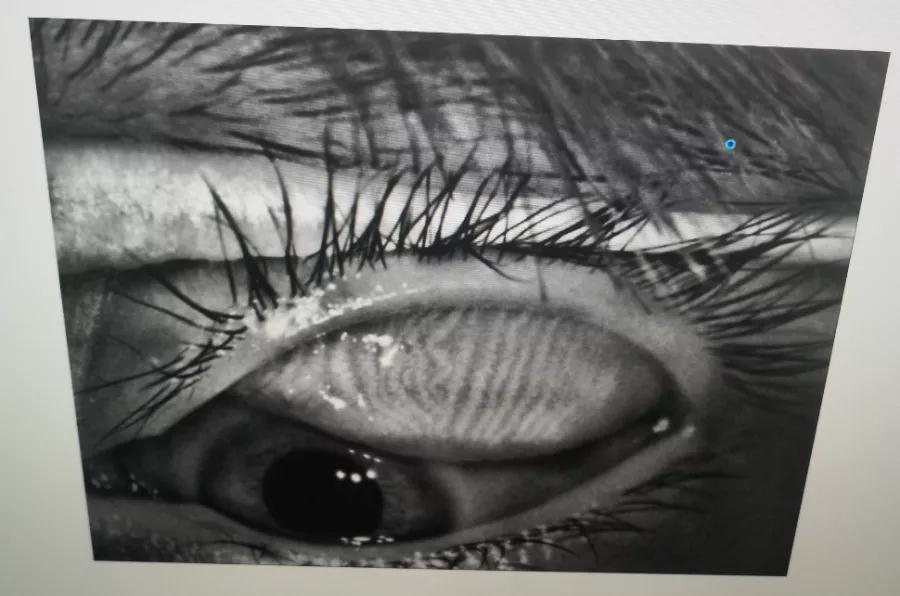

瞼板腺是排列在我們上下眼皮里面,分泌油脂的腺體,這些油脂是組成淚液的重要成分,可以讓淚水更長(zhǎng)時(shí)間的停留在眼球表面。瞼板腺油脂減少,淚水蒸發(fā)就會(huì)加快,眼球暴露在外的時(shí)間變長(zhǎng),會(huì)加重眼睛干澀,時(shí)間一久,干眼也就隨之而來(lái)。

通過(guò)熱敷并按摩擠壓上下眼瞼,將瞼板腺內(nèi)不能自行排出的分泌物推出,疏通堵塞的瞼板腺開口。

熱敷可以促進(jìn)眼周部位的血液循環(huán),瞼板腺按摩能有效改善瞼板腺功能,解決絕大多數(shù)干眼患者油脂分泌不足問(wèn)題。

通過(guò)強(qiáng)脈沖光高溫消除蠕形螨蟲,同時(shí)脈沖光產(chǎn)生的熱量可以熔解軟化瞼酯,改善瞼板腺內(nèi)脂質(zhì)分泌物的流動(dòng)性,疏通瞼板腺,提高淚膜的穩(wěn)定性,恢復(fù)正常眼表功能和眼部“鎖水”能力,從病因上治療干眼。